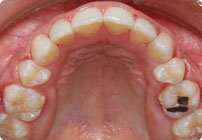

Femenino

Despues

Caso: 12 años

Adolescente: Clase II

Dental Maxilar Protrusion

Extract U4’s/L5’s

4 series de alambres:

.016″, 022″, .0215″ x .028″, .019″ x .025″ Trenzado

Elástico clase 2 2oz. TP amarillos y verdes

Retenedores: Interior Fijo de TMA y Hawley en superior

Tiempo de tratamiento: 15 Visitas